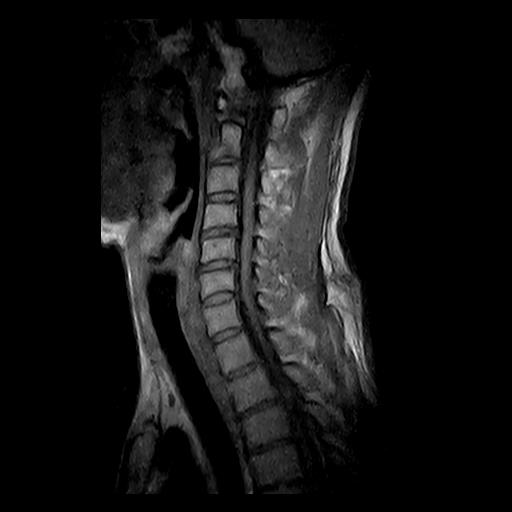

MRI(エムアールアイ)とは核磁気共鳴画像法(Magnetic Resonance Imaging)のことで、「磁気共鳴」という現象を利用して、体内の様子を画像化する原理です。原理について詳しく説明すると長くなってしまうので、今回は省略しますね。この原理を利用している検査がMRI検査になります。

そこで当院が導入しているのが、左右が開いて視界が広い“オープン型(開放型)MRI”です。トンネル型(筒状)とは異なる開放的な構造により、狭い空間に入らずに検査を受けられるため、圧迫感や不安感がぐっと和らぎます。写真に写っているのは実際の当院のMRI室です。